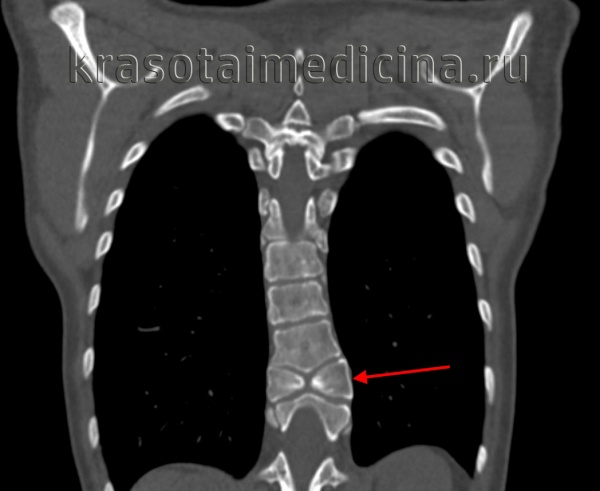

(Слева) На рентгенограмме пояснично-крестцового отдела в прямой проекции (исследование выполнено по поводу болевого синдрома в нижней части спины) случайной находкой стало неполное заращение пластинки дуги S1.

(Справа) На аксиальном Т1-ВИ видно типичное неполное слияние задних элементов позвонка по срединной линии. Эта находка стала случайной в ходе проведения обследования пациента по поводу болевого синдрома в нижней части спины. (Слева) КТ, фронтальный срез: признаки косого асимметричного расположения пластинок дуги L5 позвонка, наслаивающихся друг на друга, — та -кая конфигурация приводит к ротационной перегрузке дугоотростчатых суставов и преждевременной их дегенерации.